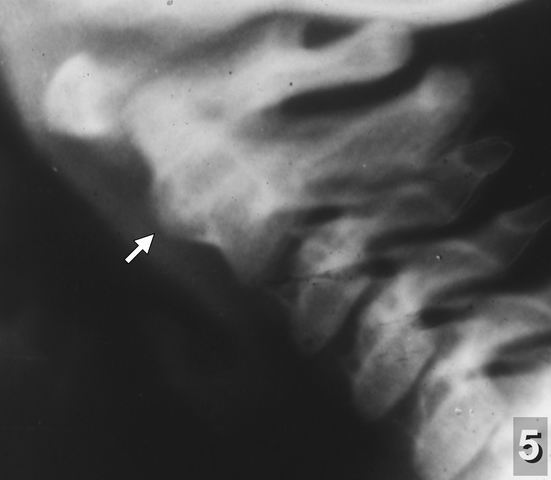

Отдаю себе отчёт в том, что эти рентгенограммы представляют интерес разве лишь для специалистов, имеющих непосредственное отношение к этой проблеме, но не для пользователей сайта "Живой Ангарск". Тем не менее, сознательно их публикую, чтобы показать диагностические возможности и важность обычной рентгенографии для выявления этой патологии. Рентгенологическое исследование шейного отдела позвоночника следует проводить детям не только при обнаружении явных клинических симптомов его поражений, но даже при подозрении на эти травмы: частота и тяжесть этих последствий несопоставимы с вредом рентгеновского облучения, получаемого младенцами при этих исследованиях. Признаки перенесённых родовых травм отчётливо обнаруживаются на рентгенограммах не только у детей грудного возраста, но и на последующих этапах их развития (рентгенограммы 5 и 6).

![]()

o" width="181" height="158" alt="Рентгенограмма 5" align="left" />Рентгенограмма 5 реб. В. 2 года. Выраженное окостенение передней продольной связки на уровне уровне синхондроза II шейного позвонка по типу костной мозоли.